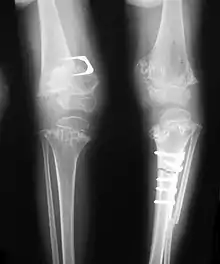

- Dysplastic/hypoplastic epiphyses especially of shoulders and around the knees.

- Metaphyseal broadening, irregularity and metaphyseal line of ossification. These abnormalities that are typically encountered in proximal humerus and around the knees are collectively known as “rachitic-like changes”.

- Radiographic lesions of the appendicular skeleton are typically bilateral and symmetric.